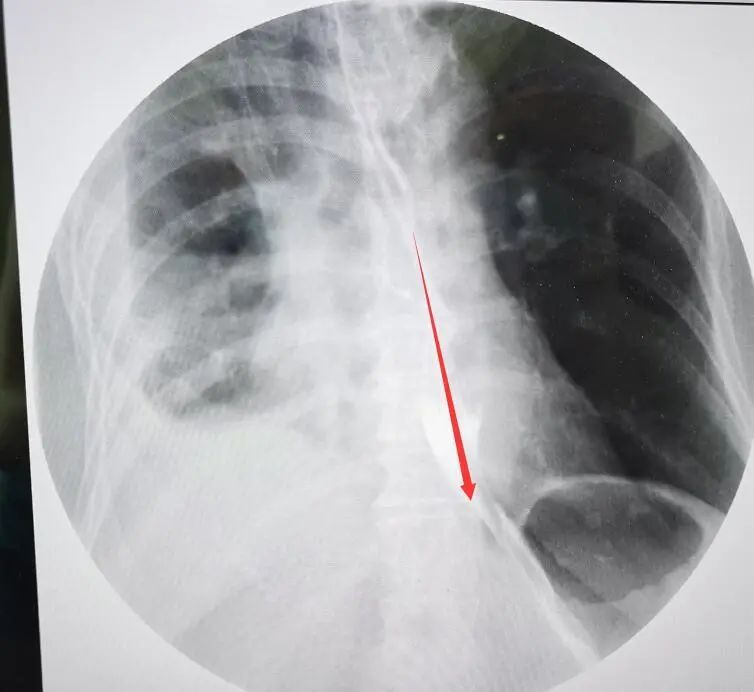

之后張奶奶就回了社區(qū)醫(yī)院掛水消炎,幾天過去,病情逐漸嚴(yán)重,呼吸困難,持續(xù)胸痛,復(fù)查CT發(fā)現(xiàn),右肺已經(jīng)被壓縮到只剩三分之一,血氧飽和度只有60%,之后緊急轉(zhuǎn)院到了南通大學(xué)附屬瑞慈醫(yī)院就診。

食管造影能夠清晰地看到造影劑漏入胸腔

根據(jù)自己多年的工作經(jīng)驗,瑞慈醫(yī)院副院長、胸外科主任曹飛接診患者后,第一時間想到了自發(fā)性食管破裂。食管造影檢查顯示,果不其然:食管中下段破裂。